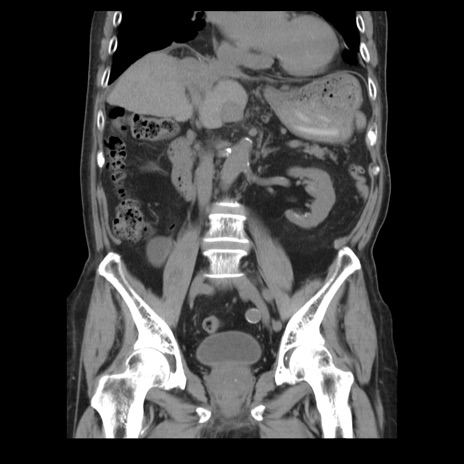

症例21(冠状断像)

【症例】70歳代男性

【主訴】腹痛

【現病歴】肝硬変・肝細胞癌にてかかりつけの方。約9時間前に食後より腹痛出現。症状が徐々に増悪し、嘔吐出現したため来院。

【既往歴】肝硬変、肝細胞癌(RFA、TACE後)

【身体所見】意識清明、表情苦悶様、BT 36℃、BP 129/78mmHg、P 88bpm、SpO2 97%(RA)、右上腹部から心窩部にかけて圧痛あり、反跳痛なし、筋性防御あり。

【データ】WBC 5800、CRP 0.16